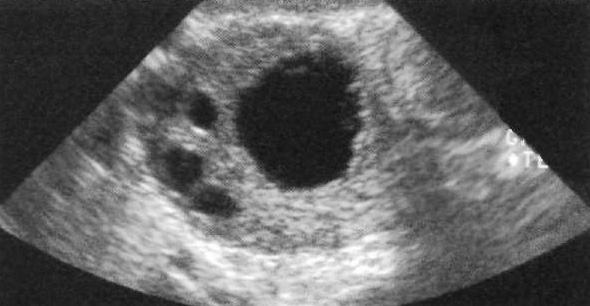

УЗИ позволяет визуализировать множественные фолликулы – эхогенные полости небольших размеров, локализованные внутри яичников (фото 1).

Фото 1. Продольный вид яичника с фолликулами в виде анэхогенных образований

Трансвагинальное или высококачественное трансабдоминальное ультразвуковое исследование позволяет определить большое количество фолликулов, особенно у женщин с низкой массой тела. Каждый менструальный цикл сопровождается увеличением одного из фолликулов, который становится доминантным. В норме доминантный фолликул может достигать диаметра до 2,5 см. Во время овуляции доминантный фолликул высвобождает ооцит, после чего становится желтым телом. Если беременность не возникла, желтое тело постепенно атрофируется. На УЗИ эта нормальная структура имеет кистозную форму, иногда с внутренним эхо или неоднородностью стенки (такая картина наблюдается, как правило, при использовании трансвагинального датчика).